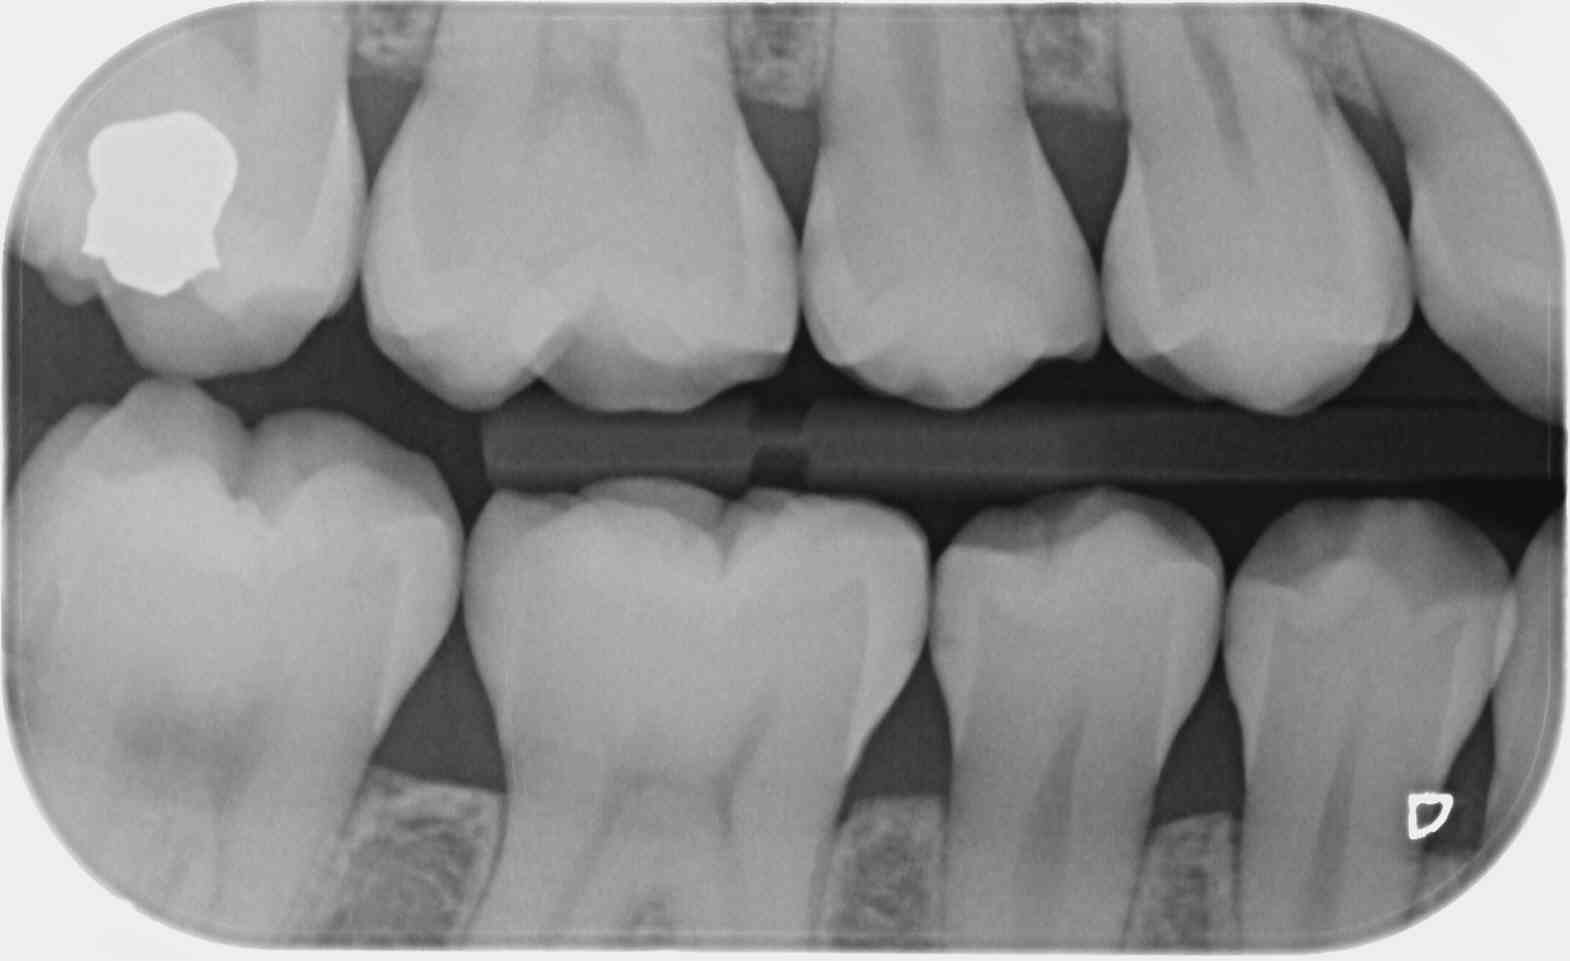

Sur un film 3+ je vois toutes les couronnes de la 7 a la 3... si je fais bite wing gauche et droit ca fait 20 couronnes, je peux compter combien de secteurs ?

C'est une faille de la CCAM qui permet, avec un peu de mauvaise foi, de coder 4 secteurs avec seulement 2 clichés, le nombre de clichés n'étant pas précisé dans le libellé.

1 radio (au singulier) en bite-wing secteur 1 et 4 = 7.98€ (HBQK389, 2 secteurs mais 1 seul cliché)

2 radioS (au pluriel) en bite-wing secteurs 1, 2 , 3 et 4 = 31.92€ (HBQK443, 4 secteurs, plusieurs clichés sans précision sur leur nombre).

T'es con d'utiliser des films taille 3 surtout avec des CDC de bonne composition. ca fait que 2 secteurs ou 4. Alors que 4 clichés ca fait 4 secteurs....ou 8. Les rétro alvéolaires sont offertes. -)

Allez un petit dernier pour la route : avec des taille 3 tu n'as pas forcément l'os alvéolaire bien visible et ça mon garçon c'est un indu. -))))

Le problème vois tu avec ces films étendus c'est que moins tu as de clichés moins tu as de dents au centre d'un cliché et moins tu as de secteurs. -)))

Effectivement. C'est pour ça que sur les patients plus âgés je sors le taille 2, qui a l'avantage de permettre l'utilisation du collimateur. Par contre, on ne peut pas avoir en même temps les canines et les DDS. Le taille 1 suffit souvent sur les patients jeunes sans DDS.